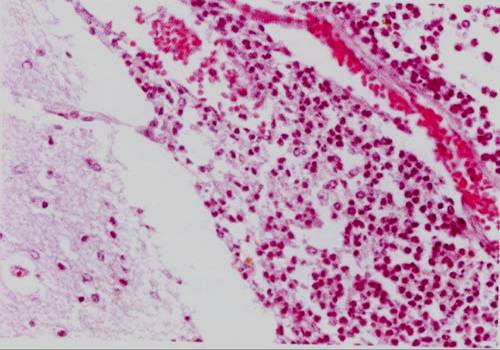

256.亚急性细菌性心内膜炎的特点除外下列哪项

赘生物单个或多个,呈息肉状或菜花状

多发生于原有病变的瓣膜上

镜下表面有细菌团

赘生物脱落引起动脉栓塞和血管炎

外观污秽,质松软、灰黄、易脱落

正确答案:C